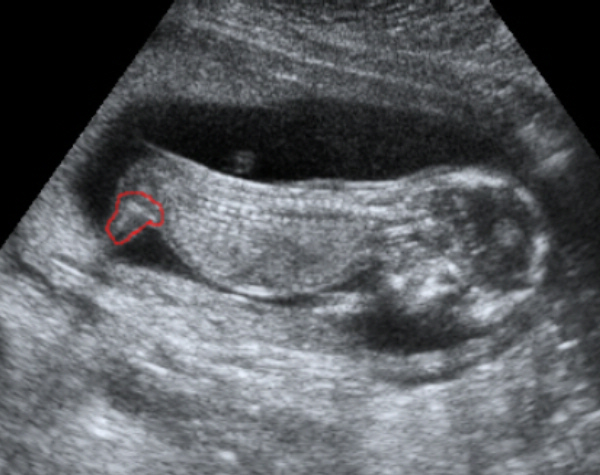

Más pozicíóban van Lizzy a képen, mint a mostani pocaklakód, így elég nehéz kitalálni... ugyanis a lányoknak is kell ott lenni fehérnek, nézd meg anya maci képét, az Ő kislányának is van, csak mondjuk sokkal kisebb, így lehet az amire gondolsz :D

Este felteszem Boti képét, Ő pont ugyan ilyen szögben van, és szintén 2d-n mint a Te pocilakód, attól okosabbak leszünk szerintem :P :wink:

Ahogy ígértem, hoztam a képeket. Igaz Ti idősebbek vagytok a képeken, mert Boti a képeken 14+6 hetes, Ti meg ugye már 17+3 :)

Dodó Pocaklakó Kép

Boti

Kép

Dodó Pocaklakó

Na mazsolázzunk... :D